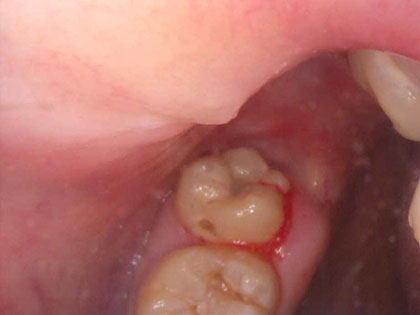

• 抜歯後の写真がこちら

• 分離鉗子、あるいはヘーベルという器具をひっかけると歯が脱臼しますので、後は引っ張れば抜けます。

• 最後に歯を抜いた部分を洗浄し、ガーゼで圧迫止血。5分程ガーゼを噛んでもらいましたら、大体のケースは止血します。